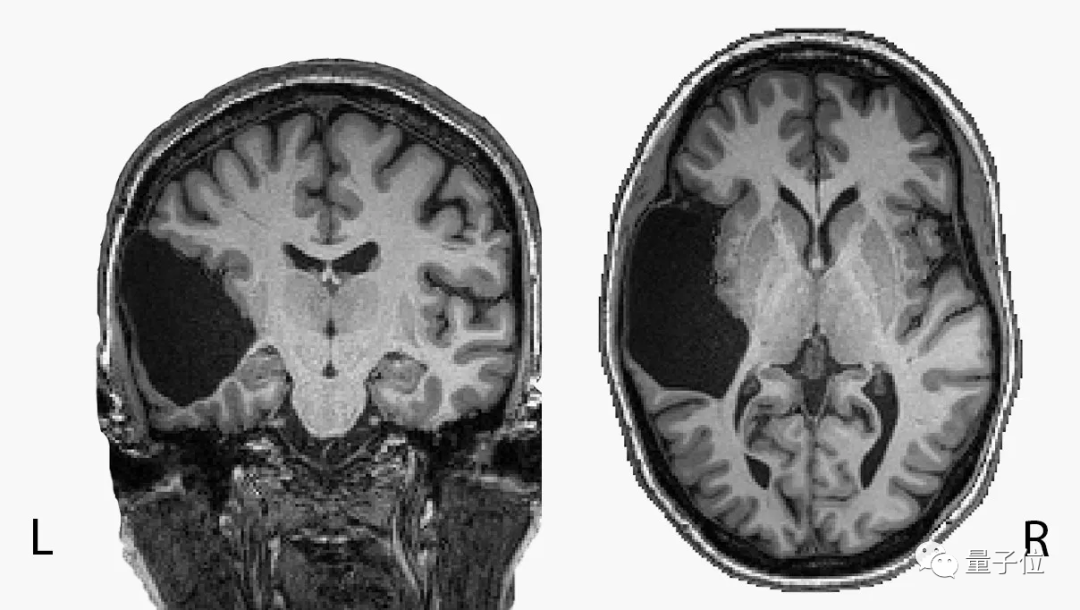

她活到25岁,才发现自己的左脑缺了一大块。

本来应该是左颞叶(temporal lobe)的地方现在只有液体,另外脑干也不完整。

对于惯用右手的普通人来说,左颞叶正是承担语言理解功能的主要脑区。

同样惯用右手的她,语言能力非但没有受损,还在语言IQ测试中排进前2%。